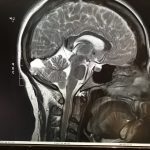

Il a fait l’examen et m’a annoncé que j’avais deux masses… celle à l’aisselle, que je n’avais pas imaginée (d’ailleurs ça a fait plutôt mal durant l’examen et même un peu après!)… et une 2e au sein du même côté.

Pendant que je me rhabillais il m’a expliqué que la masse au sein pouvait être simplement du tissu cicatriciel accumulé (j’ai eu une réduction mammaire il y a environ 15 ans)… ou autre chose de bénin… mais qu’on ne pouvait pas prendre de risque et qu’il fallait vérifier.

Je suis donc ressortie du bureau avec un papier pour aller passer une mammographie diagnostique.